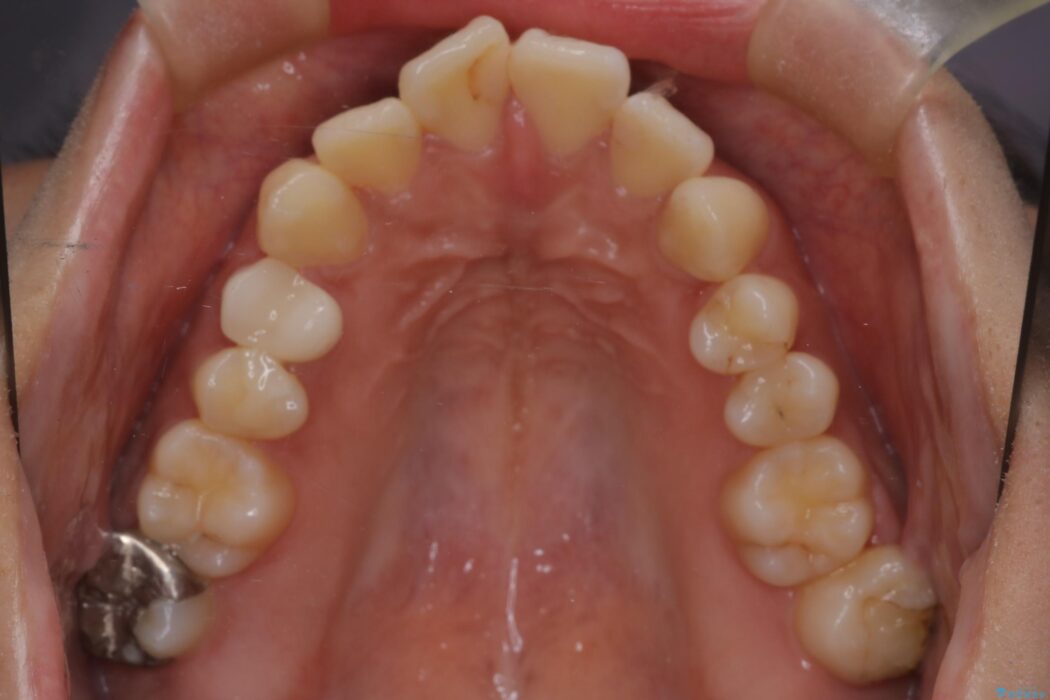

口元の突出感が解消し、Eラインが劇的に改善しました。機能的な噛み合わせと美しい審美性を両立し、理想の口元を獲得していただけました。

そこで、上下左右の第一小臼歯(4番目の歯)を計4本抜歯し、そのスペースを利用して前歯全体を奥へ移動させる抜歯矯正の治療計画を立案。